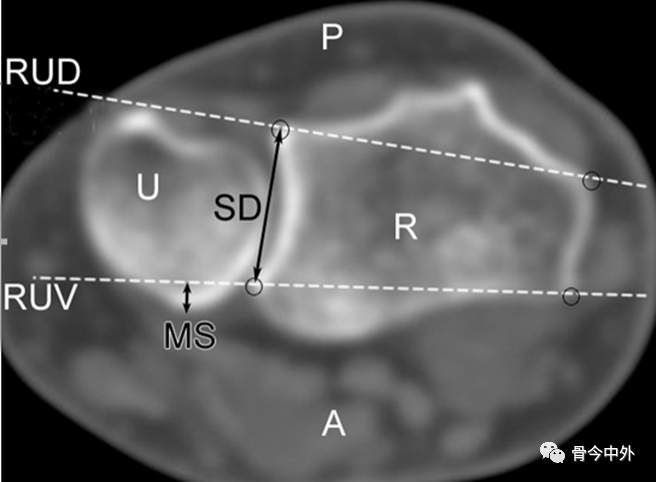

图10 Nakamura法桡尺远侧关节半脱位CT诊断(CT横断面)。只有MS大于1/4SD时,可诊断为半脱位。MS:尺骨半脱位部分的最大宽度;RUD:桡尺背侧连线;RUV:桡尺掌侧连线;SD:乙状切迹的直径;U:尺骨;R:桡骨;P:背侧;A:掌侧。(注意:扫描时,肘关节伸展,前臂最大程度旋前或旋后)。